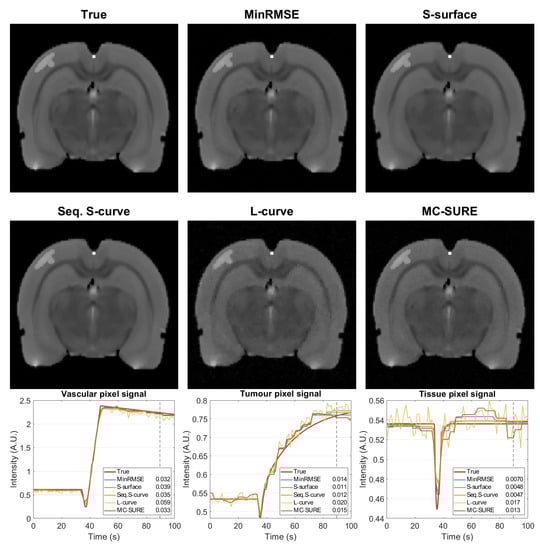

4.2. Experimental Data